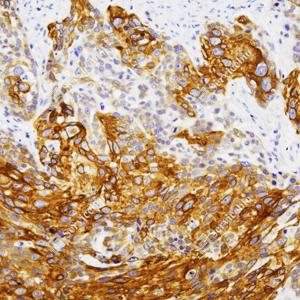

IHC检测Cytokeratin 6蛋白(货号 GB151247). 样品: 人食管癌, 4%多聚甲醛 (货号G1101) 固定12-24小时. 抗原修复: 柠檬酸抗原修复液(干粉, pH 6.0) (G1201), 高压锅均匀喷气计时2分钟. —抗: 1: 700稀释, 4℃ 孵育过夜. 二抗: HRP标记山羊抗兔IgG (H+L) (货号GB23303), 1: 200稀释, 室温孵育1小时. |